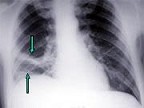

- 多项选择题该病人突发胸部疼痛,进行性呼吸困难, 行X线片检查,提示右下肺病变, 急诊CT平扫加增强,如图所示 ( )

A、X线片示右下肺实变影

D、考虑为右侧肺动脉(中央性)栓塞